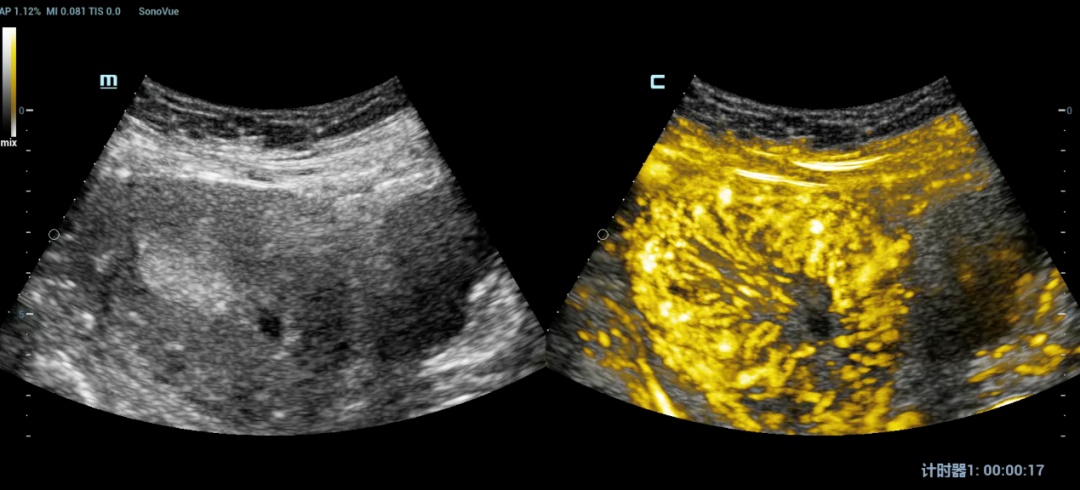

5.子宫内膜静脉造影:判断内膜的微循环灌注,有无血供异常情况。

子宫内膜静脉造影图例:可见内膜血供灌注僵直,血管走形变异